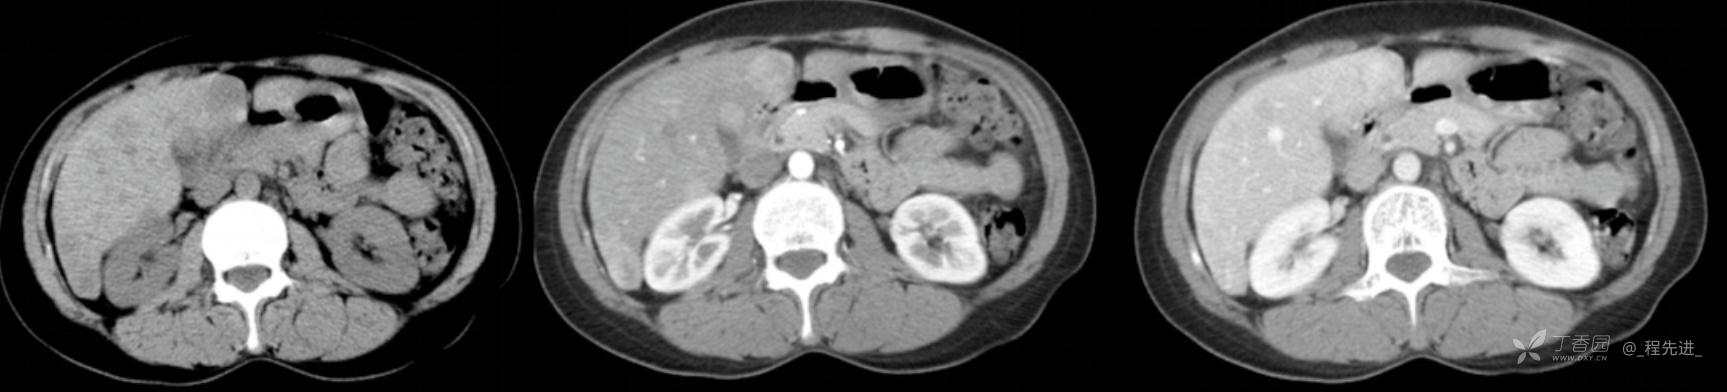

图像左边为平扫,中间的是动脉期,右边的是静脉期